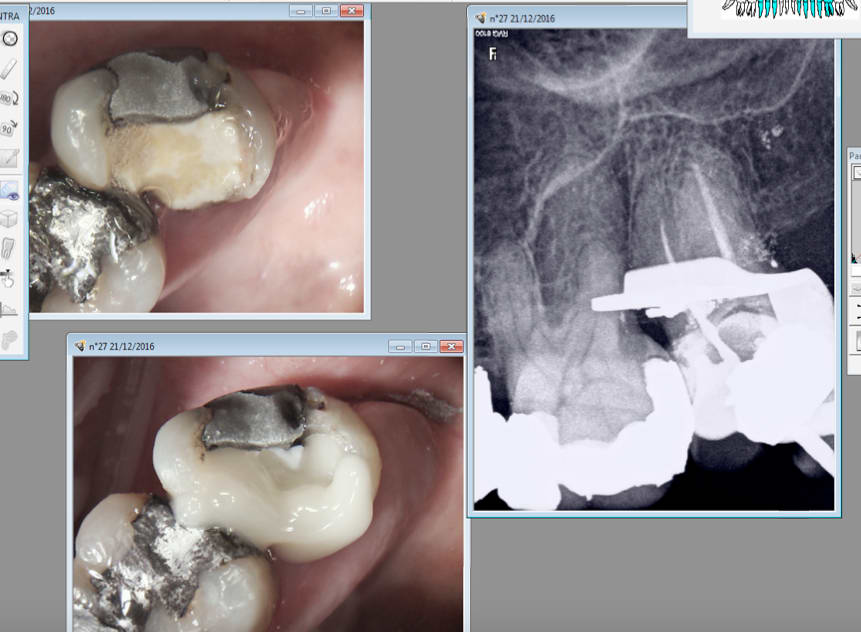

Impossible de traiter ces canaux vestibulaires de cette 7 avec les premiers. Situation débloquée instantanément avec les seconds. -)

pas moyen d'aller plus loin que ca avec les premiers. Avec le sx gold c'est descendu tellement vite que j'ai cru faire un faux canal. -)